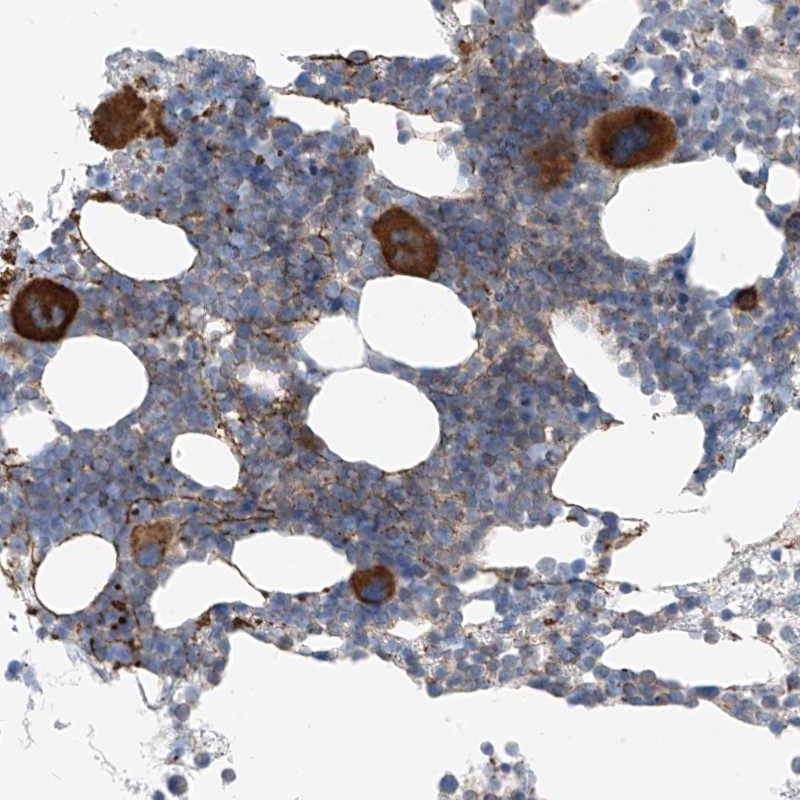

Immunohistochemical staining of human bone marrow shows strong cytoplasmic positivity in megakaryocytes.